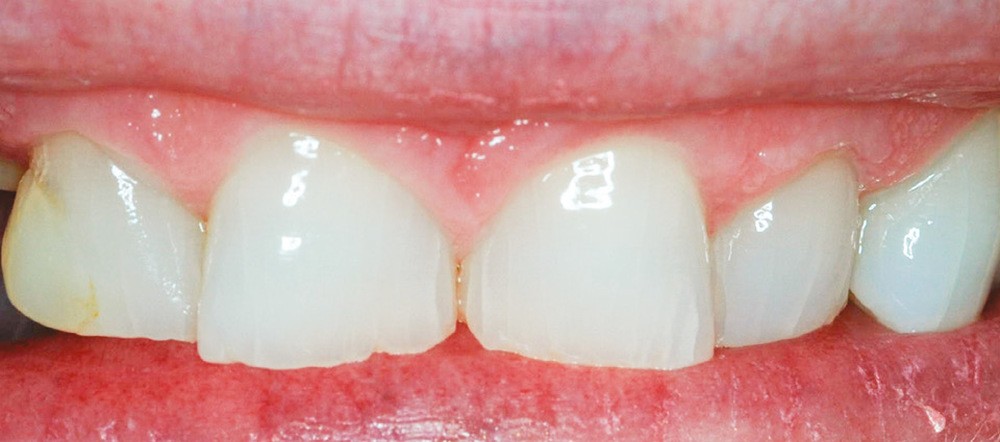

Même en l’absence de restauration, l’espace biologique n’est parfois naturellement pas correctement établi sur la dent. Ce phénomène est couramment décrit comme une éruption passive retardée. Elle peut être une indication d’élongation coronaire esthétique afin de rétablir la couronne clinique dans son intégralité (fig. 2a-c).